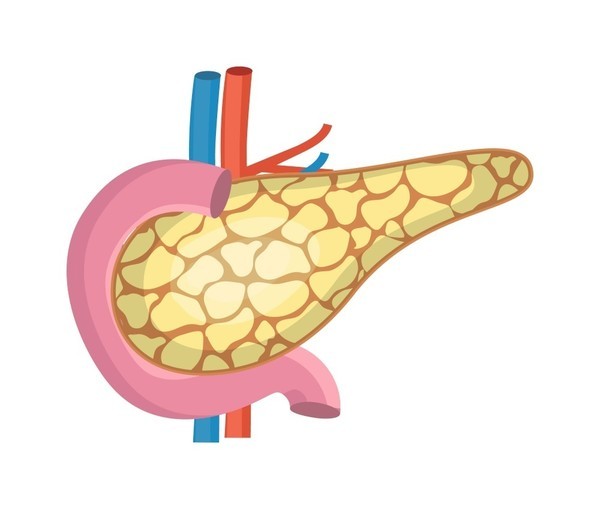

췌장은 지방을 분해하는 효소를 생성하는 내분비 기관으로, 췌장에 문제가 생기면 지방이 함유된 음식을 소화하기 어려울 수 있습니다. 아보카도나 견과류와 같이 지방 함량이 높은 음식을 먹으면 복부 불편감을 느낄 수 있으며, 지방이 많이 함유된 음식을 먹으면 흡수되지 않은 지방이 장에서 설사를 유발할 수 있습니다.

보통 혈당 관리에 신경 쓰시는 분들은 대개 당뇨병을 앓고 계신 분들인데, 췌장의 건강 관리가 중요합니다. 췌장이 자체적으로 형성하는 세포 중에는 인슐린을 생성하는 베타세포가 있는데, 이 베타세포는 혈당을 담당하는 인슐린을 합성, 저장, 분비하는 역할을 합니다. 하지만 췌장염이나 췌장암이 생기면 이러한 베타세포가 파괴되기 때문에 혈당관리를 잘하던 사람도 혈당관리에 어려움을 겪으며 심한 당뇨병에 걸릴 수 있으므로 당뇨병의 형태를 중심으로 췌장의 건강을 항상 체크할 필요가 있습니다.